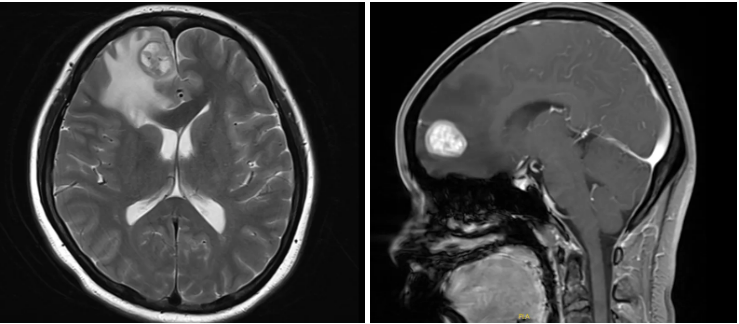

2025年5月头颅MR

右侧额叶占位(约24mm×18mm),考虑转移瘤。

脑转移瘤局部手术治疗

神经外科会诊考虑患者为孤立性脑转移瘤,且存在明显占位效应,符合局部手术治疗条件,于2025-5-20行“右侧额叶占位显微切除+人工硬脑膜修补+颅骨骨瓣修补术”。